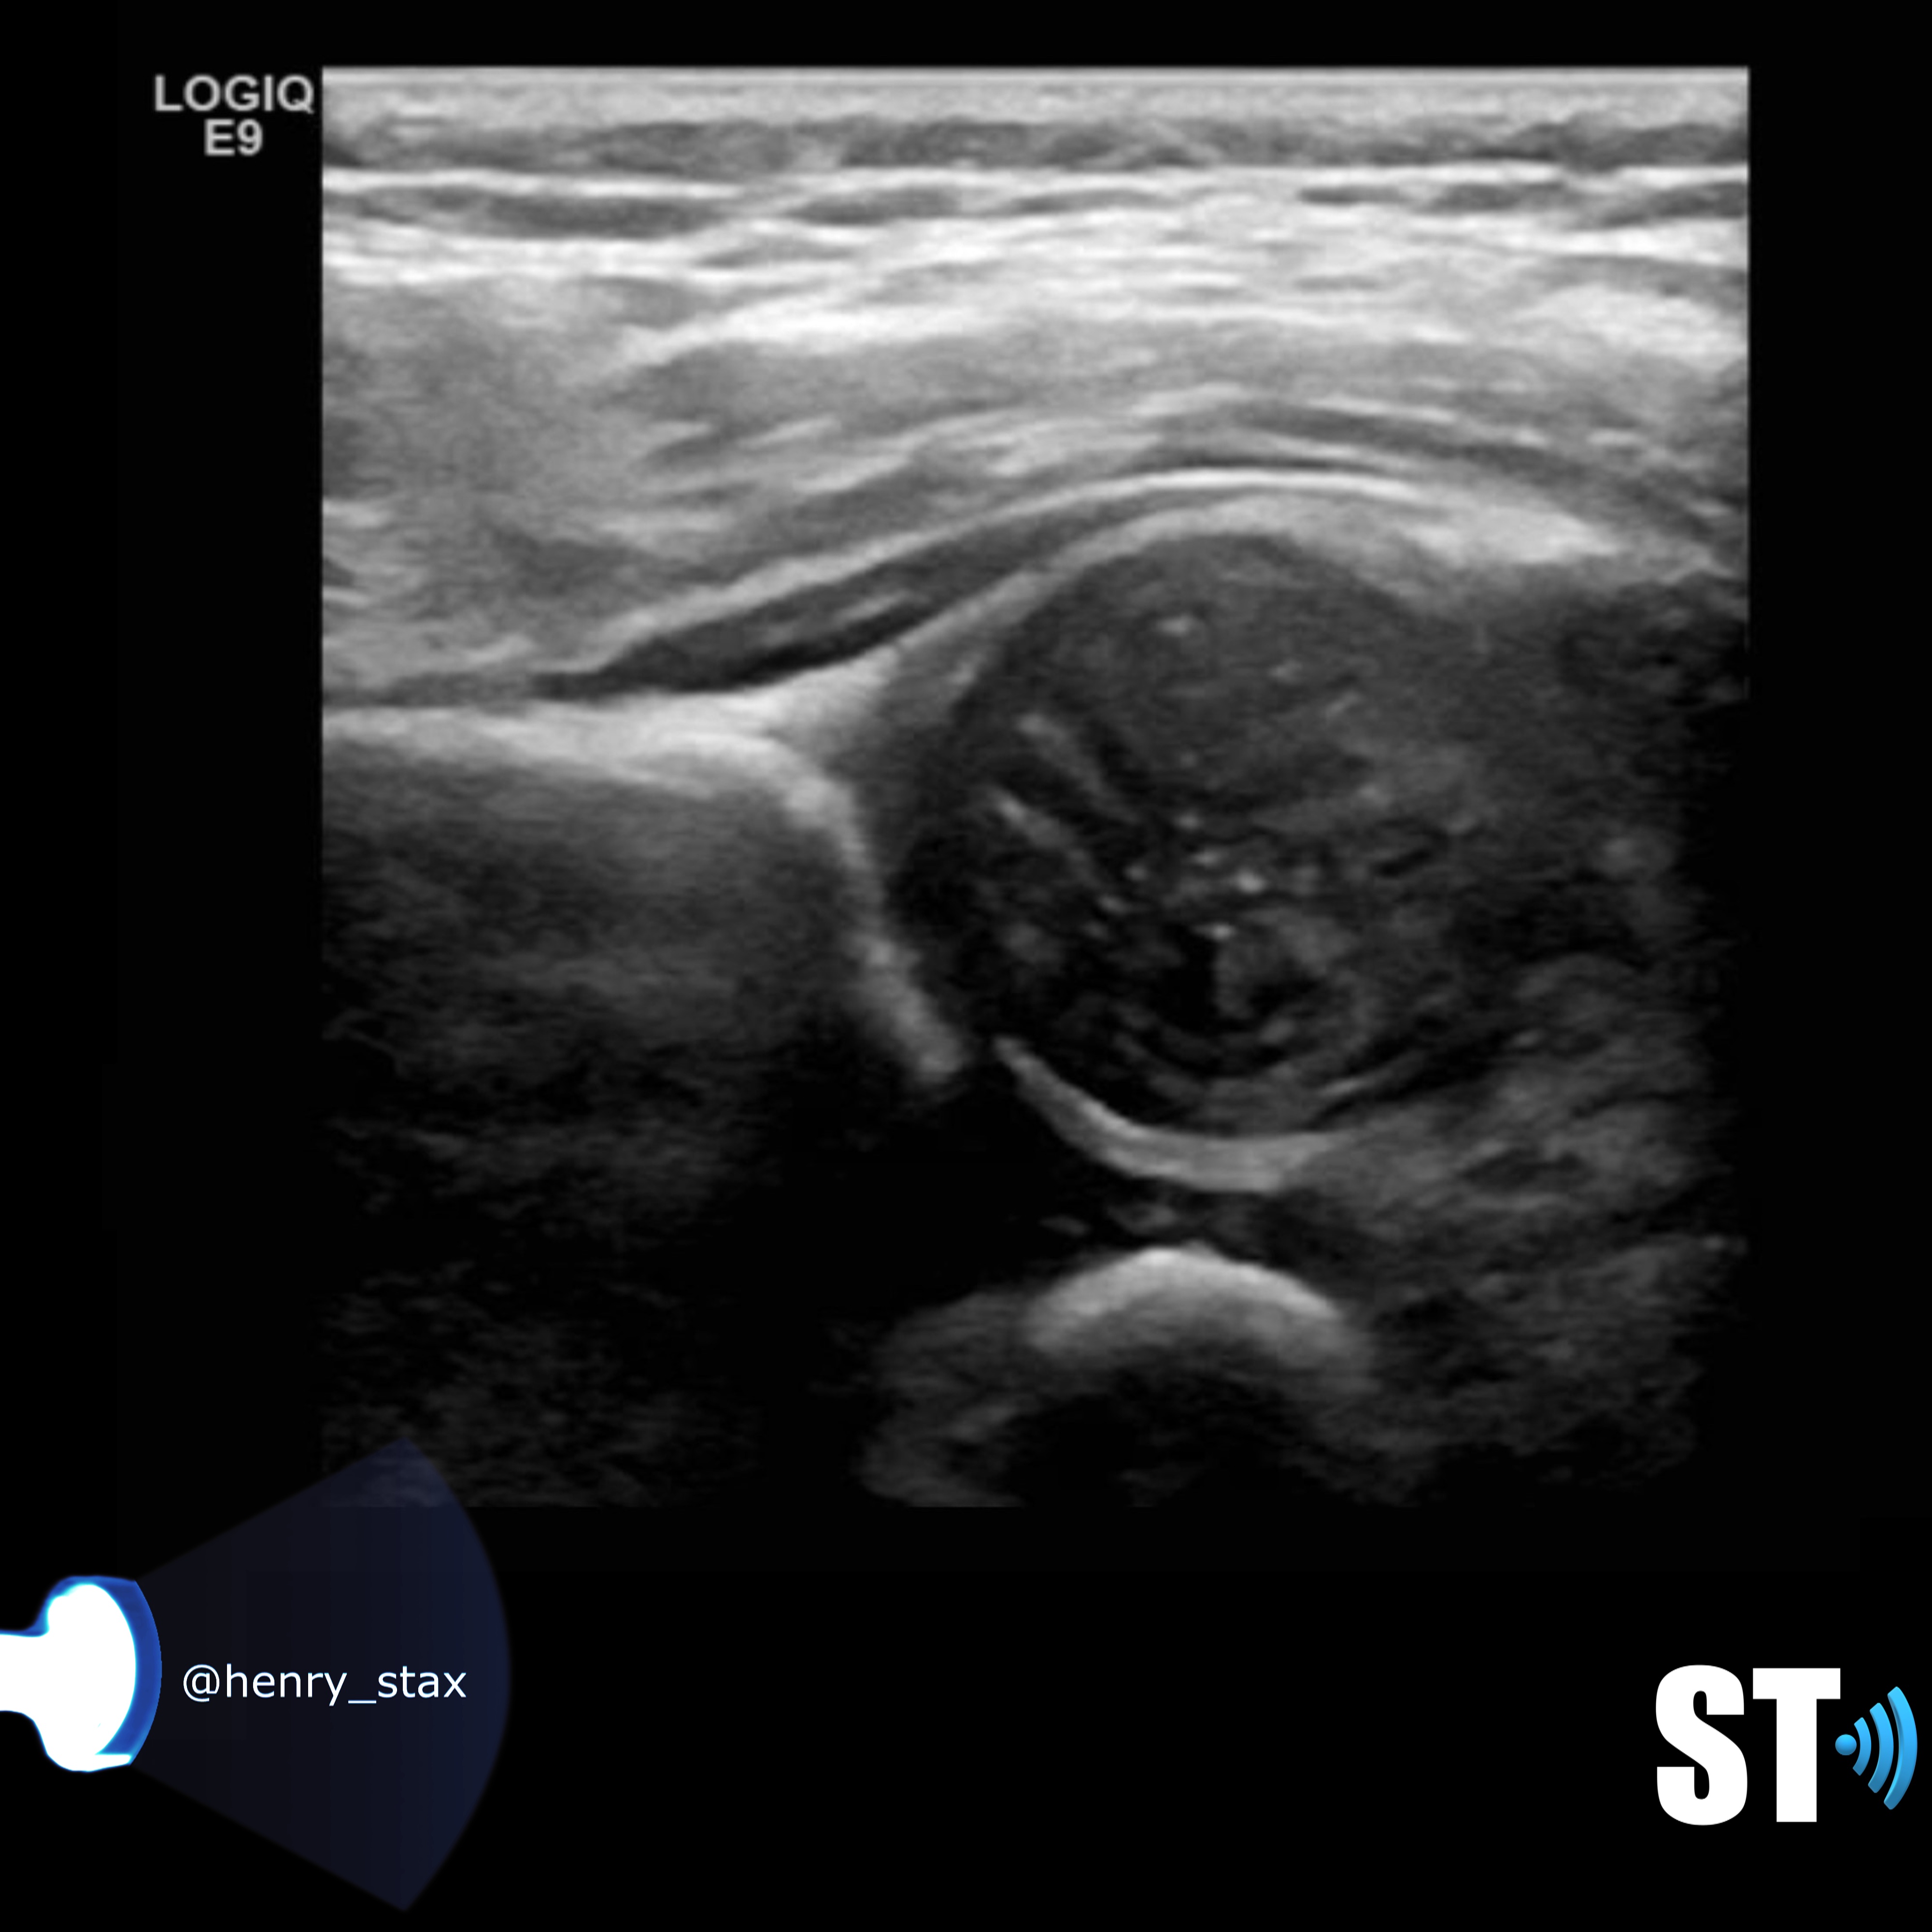

From www.bmj.com

Coronal ultrasound anatomy of a normal hip in a newborn baby The BMJ Baby Hip Ultrasound Protocol Ultrasonography (us) is a useful screening method for the diagnosis of developmental dysplasia of the hip (ddh) and congenital spinal anomalies in. See the normal anatomy, angles, criteria and limitations of the. It affords direct visualization of the cartilaginous and other. A stepwise approach will be shown in this article. Developmental dysplasia of the hip is a congenital disorder in. Baby Hip Ultrasound Protocol.

From sonographictendencies.com

Neonatal Hip Ultrasound Sonographic Tendencies Baby Hip Ultrasound Protocol Learn how to perform and interpret paediatric hip ultrasound images for neonates. It affords direct visualization of the cartilaginous and other. See the normal anatomy, angles, criteria and limitations of the. A comprehensive guide for clinicians, radiographers and radiologists who perform and report on paediatric hip scans using ultrasound imaging. Ultrasonography (us) is a useful screening method for the diagnosis. Baby Hip Ultrasound Protocol.

Neonatal Hip Ultrasound Sonographic Tendencies Baby Hip Ultrasound Protocol A stepwise approach will be shown in this article. The graf method is the most widely used ultrasound technique for infant hips; This document provides guidelines for the performance and recording of ultrasound examinations for detection and assessment of. It affords direct visualization of the cartilaginous and other. Learn how to perform and interpret paediatric hip ultrasound images for neonates.. Baby Hip Ultrasound Protocol.